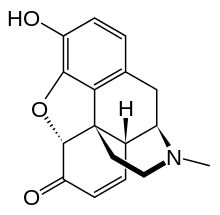

Others

- 1-Nitroaknadinine * 14-episinomenine

- 5,6-Dihydronorsalutaridine

- 6-Keto Nalbuphine

- Aknadinine

- Butorphanol

- Drotebanol

- Nalbuphine

Structures

| Other Morphinans | ||||

|---|---|---|---|---|